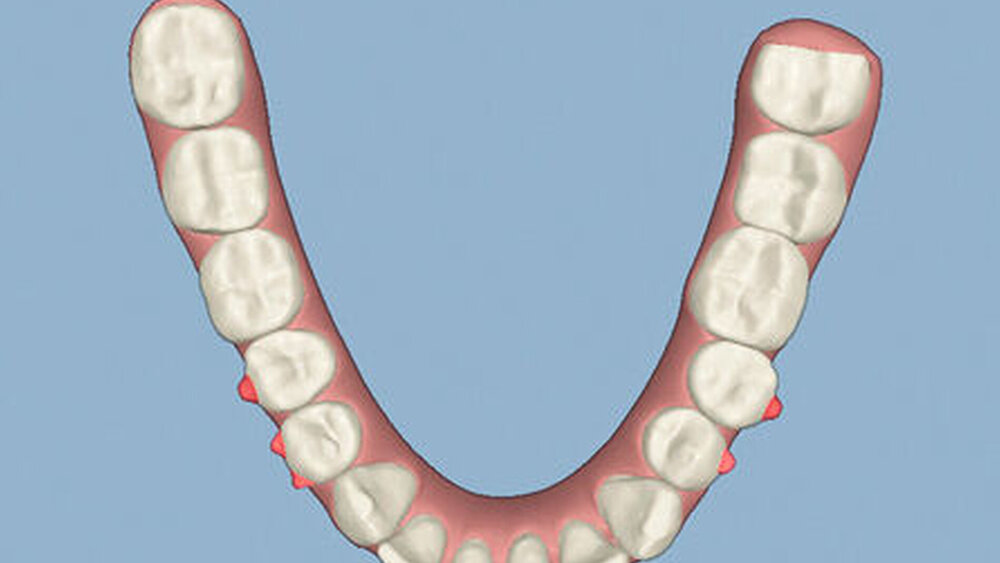

Kieferorthopädisch imponierte beidseits eine neutrale Verzahnung bei einem tiefen Biss von 5 mm – bedingt durch die Verlängerung beider Frontzahngruppen. Besonders Zahn 11 zeigte eine erhebliche Verlängerung und Protrusion mit einer sagittalen Frontzahnstufe von 5 mm. Sowohl die Frontzähne im Ober- als auch im Unterkiefer wiesen eine lückige Beziehung zueinander auf (Abbildung 1).